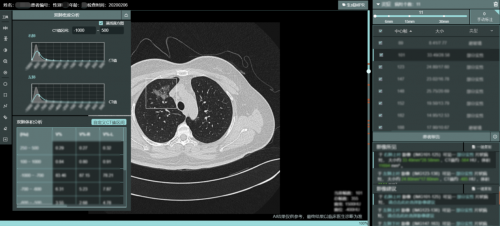

点内科技在原有强大的肺部 AI 辅助诊断系统的基础上,对新型冠状病毒肺炎筛查进行了专门的强化,可以早期发现散发的磨玻璃影,针对早期炎症做出快速准确的检测,同时提供双肺密度、双肺体积分析等参数对患者双肺的总体感染情况做直观的展示,协助医生对病情进行多维度评估,随访对比功能可以很好的观察到同一病灶在不同时间的变化情况,用于新冠肺炎早期的大规模病例影像筛查,检出率高,可以快速对无症状感染者和早期患者进行鉴别和排查,有助于疫情的防控。同时为保障系统更有效的服务一线,点内团队也制定了迭代计划,依据现场使用情况及时做出优化,为战“疫”保驾护航!

点内科技肺炎 AI 辅助筛查系统采⽤ CT 影像处理和人⼯智能深度学习技术,将 AI 应⽤到肺部 CT 影像识别和辅助诊断。早先出现新冠肺炎病毒携带者多次核算检测呈现阴性导致漏诊而出现家庭聚集发病的案例。肺炎特别版优势在于快速检测到早期病变,如散发的磨玻璃影,高效准确的发挥 CT 辅助诊断,可以快速对无症状感染者和早期患者进行鉴别和排查。同时 AI 加快了医生的诊断速度,减少了患者排队时间,降低了患者交叉感染的风险。